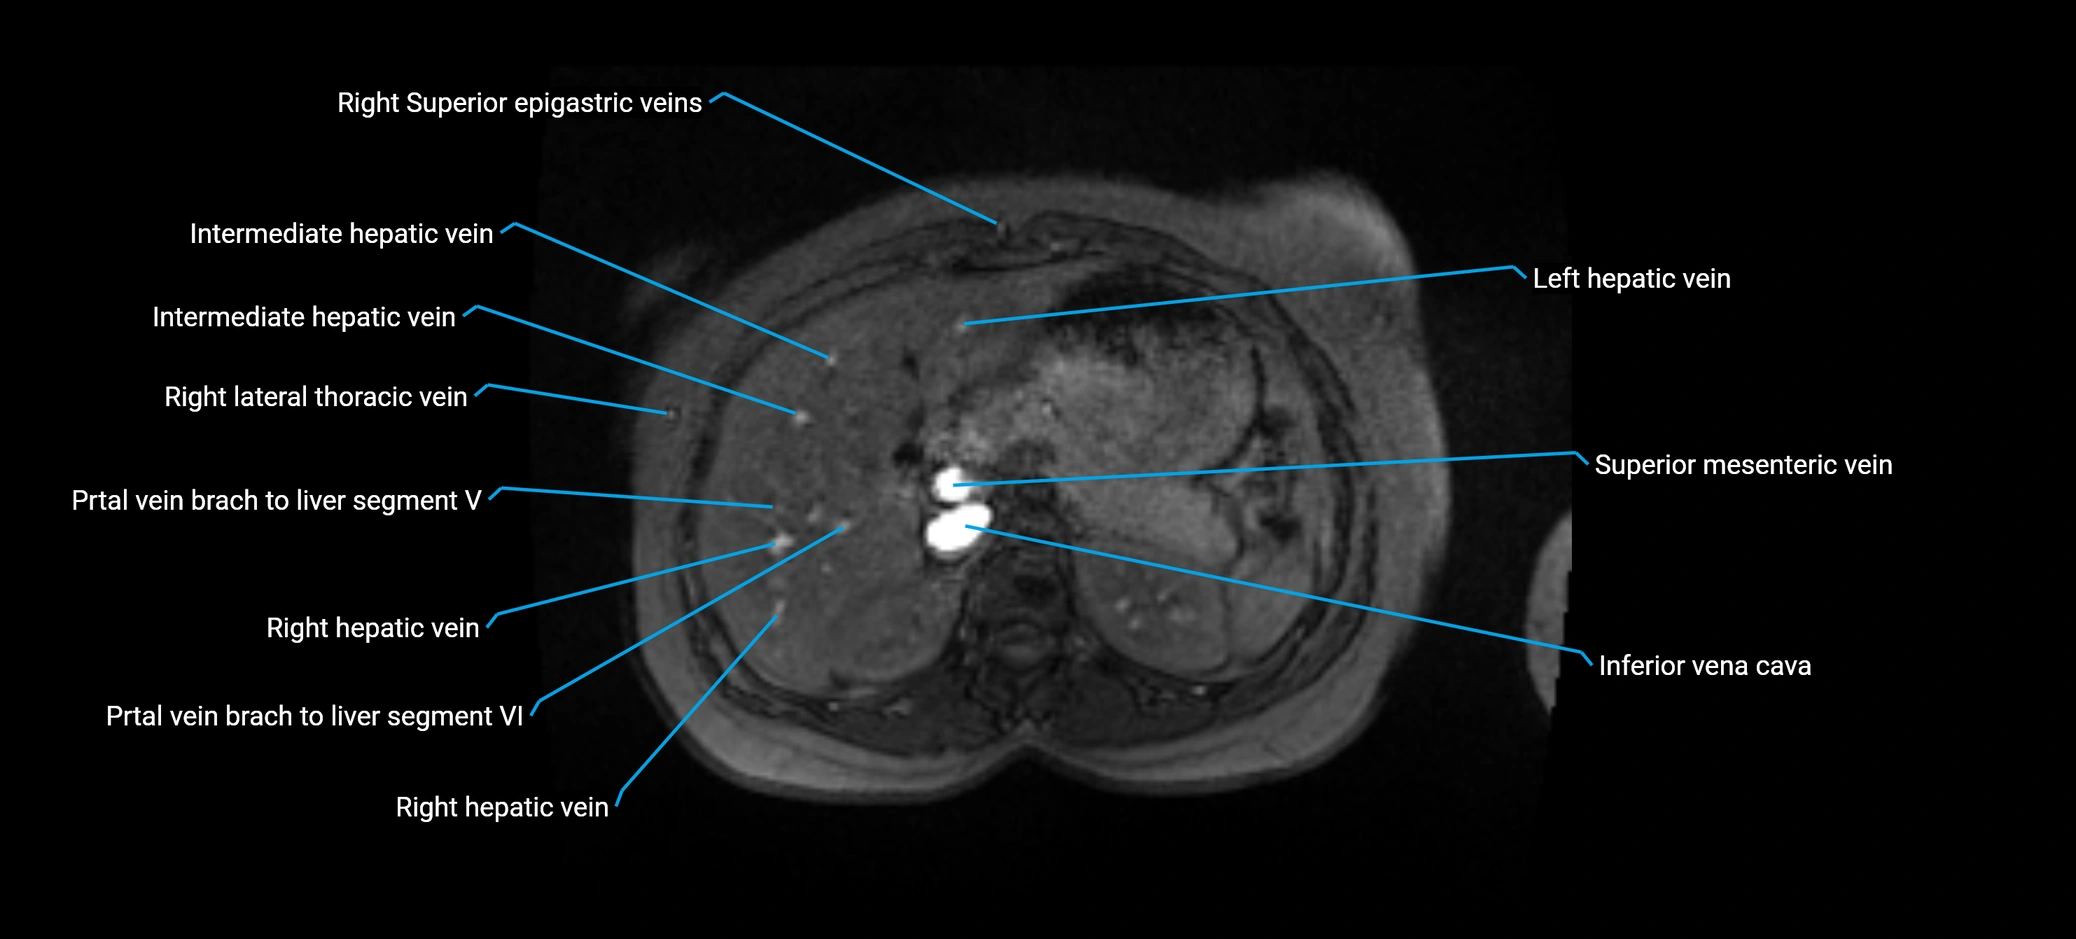

MRI image

image